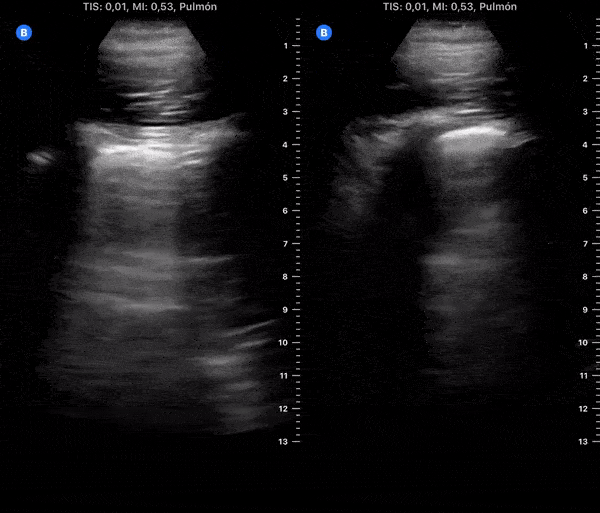

COVID 19 Lung US Disease Progression - Day 14

Day 14 after #COVID diagnosis. Less symptoms - cough, weakness, nausea, light headache. Regaining appetite/smell. No fever/dyspnea. SpO2 98%. #POCUS update: Improving - thick pleura & Bilateral scattered B-lines, no effusion. @yaletung